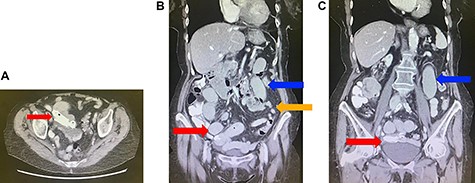

(A) Axial view of computed tomography (CT) of the abdomen demonstrating migration of the biliary stents into the small bowel (red arrow). (B) Coronal view of CT of the abdomen demonstrating migration of the biliary stents into the small bowel (red arrow), with dilated (blue arrow) and collapsed (orange arrow) loops of small bowel suggestive of a small bowel obstruction. (C) Coronal view of CT of the abdomen demonstrating migration of the biliary stents into the small bowel (red arrow) and dilated loops of small bowel (blue arrow).